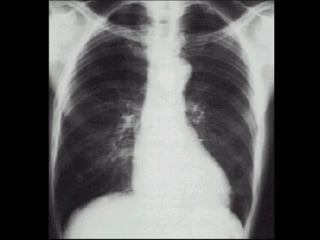

COMPLICACIONES HIPERTENSIVAS: Hipertrofia Ventricular Izquierda Disfunción Diastólica Disfunción Sistólica Insuficiencia Cardiaca Izquierda, Derecha Cardiopatía Isquémica

COMPLICACIONES HIPERTENSIVAS: HipertrofiaVentricular Izquierda Disfunción Diastólica Disfunción Sistólica Insuficiencia Cardiaca Izquierda, Derecha Cardiopatía Isquémica

COMPLICACIONES ATEROSCLERÓTICAS: CardiopatíaIsquémica Enfermedad Vascular Cerebral Enfermedad Vascular Periférica